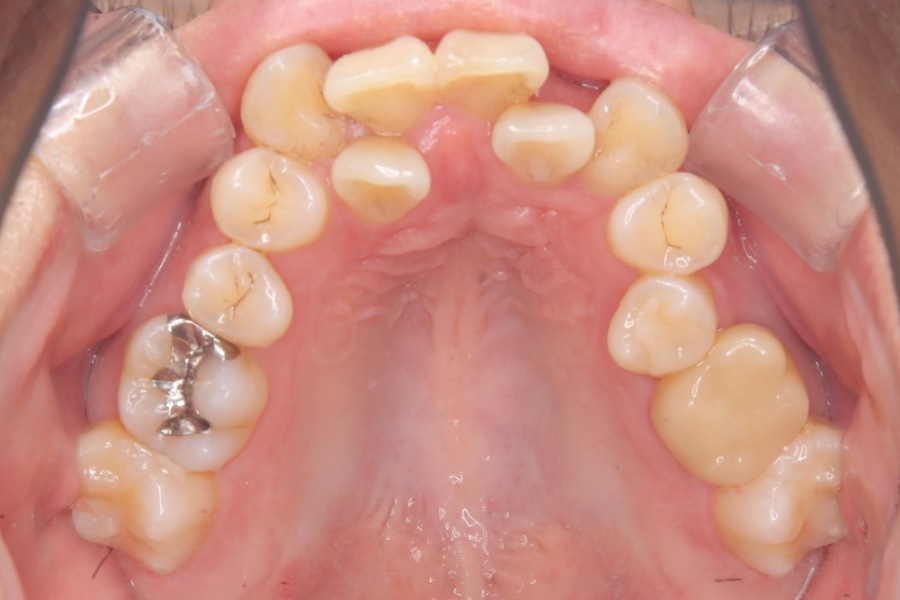

治療後

主訴 歯全体のガタつきが気になる

治療内容 インビザライン矯正

小臼歯抜歯